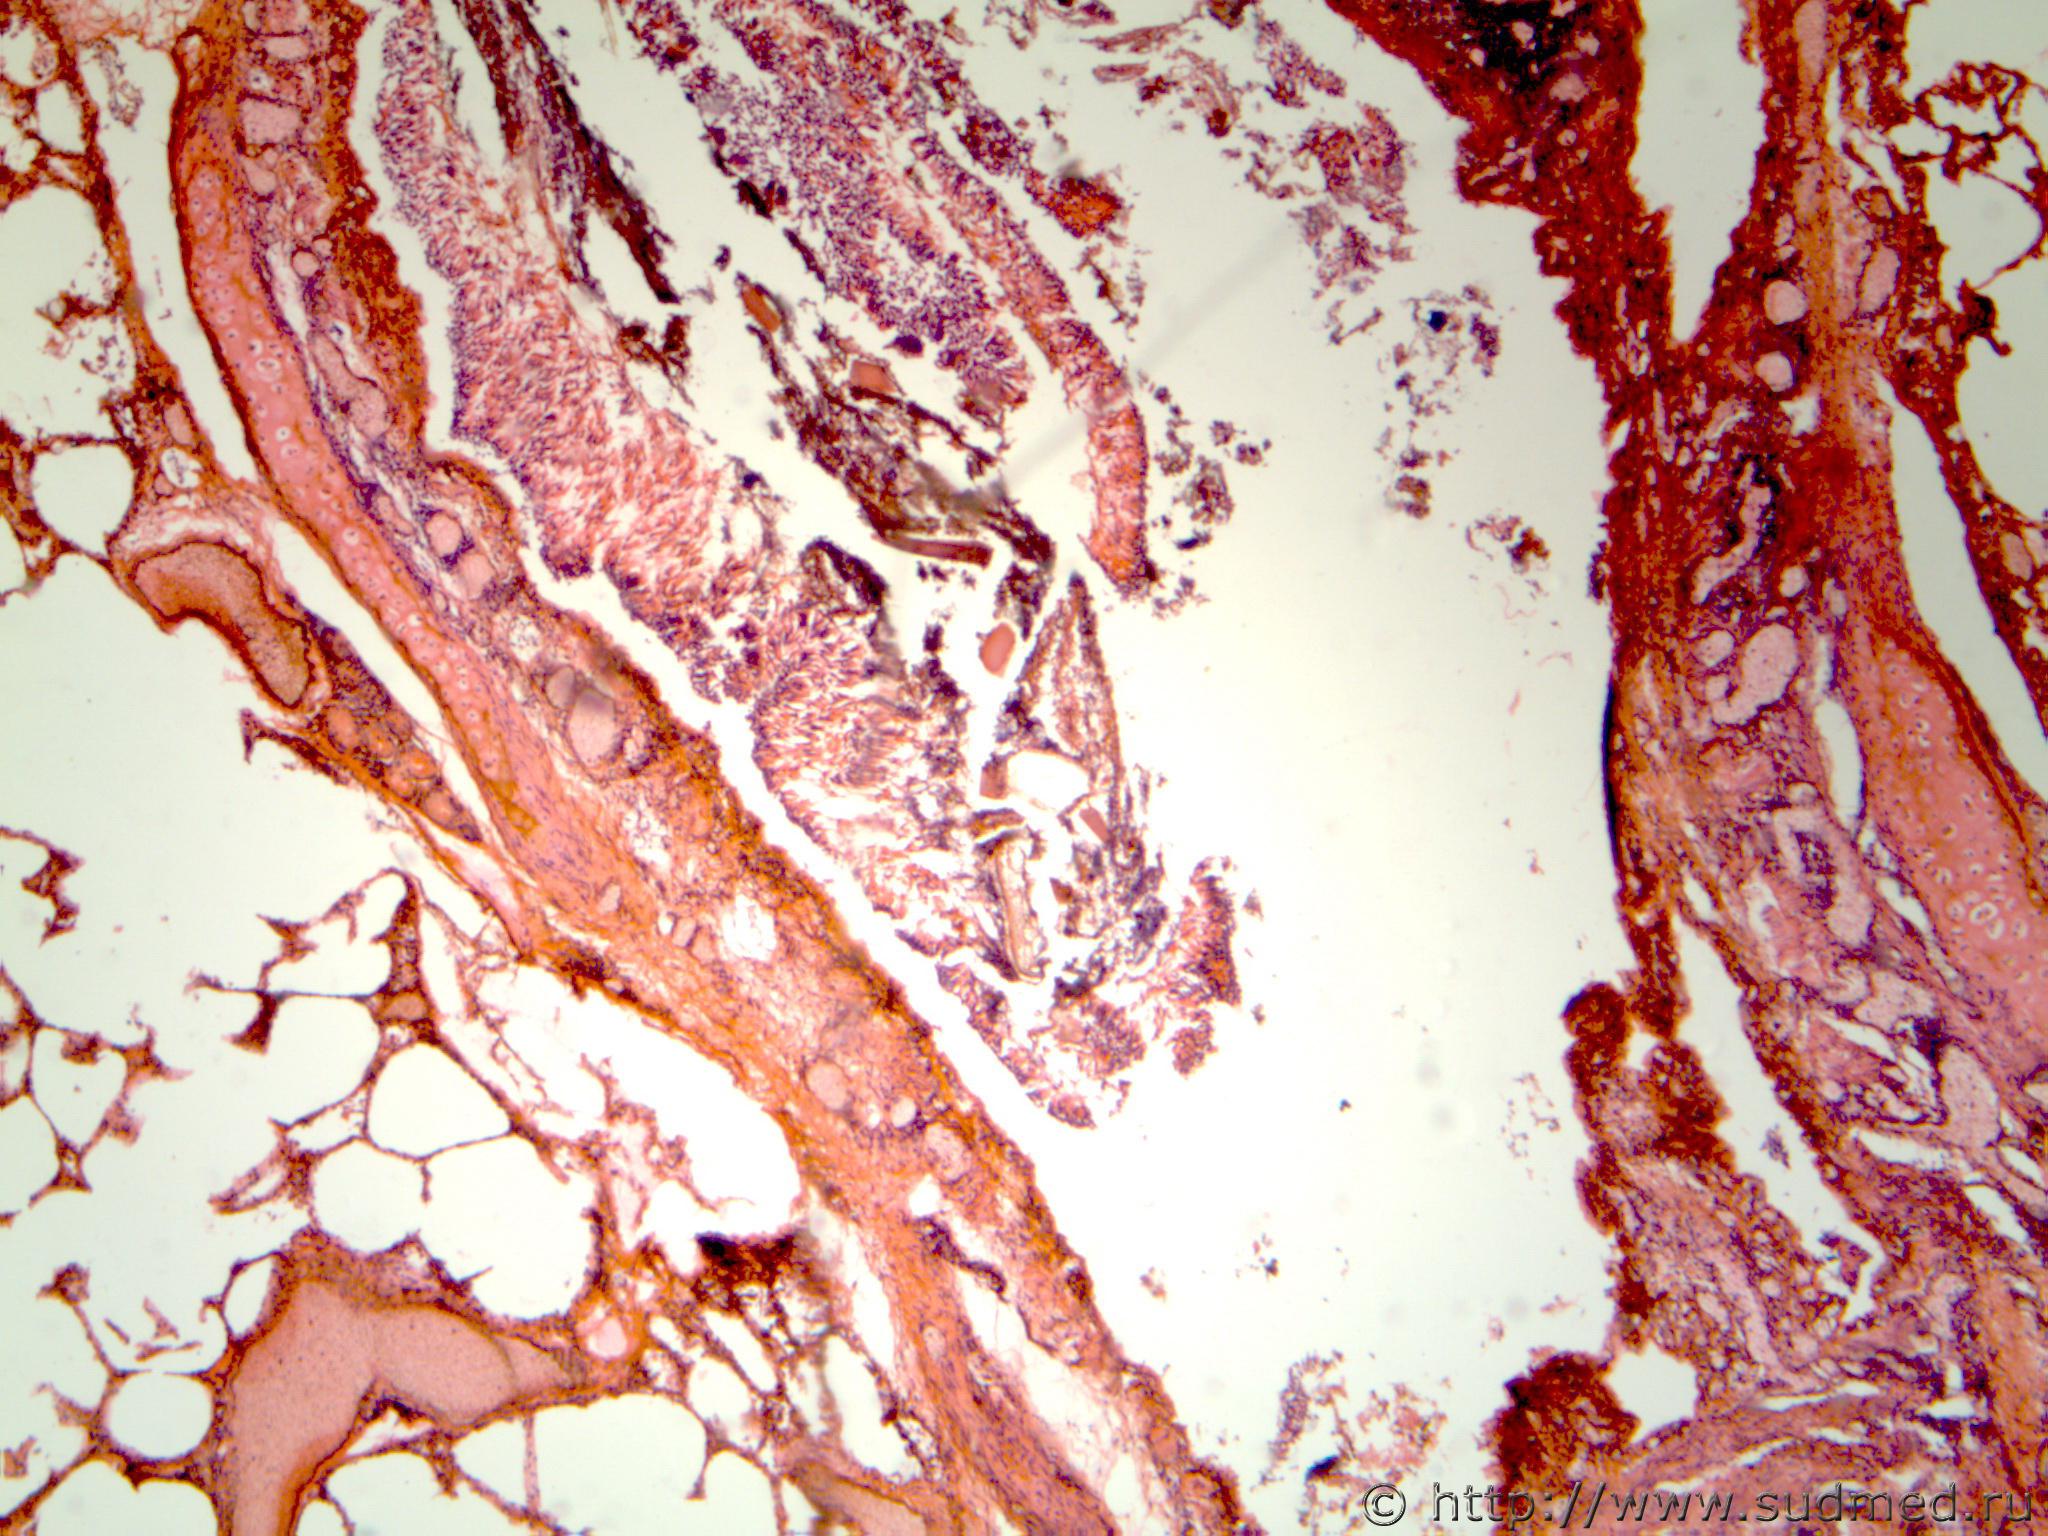

Аспирация ЭОВ (роговыми чешуйками)